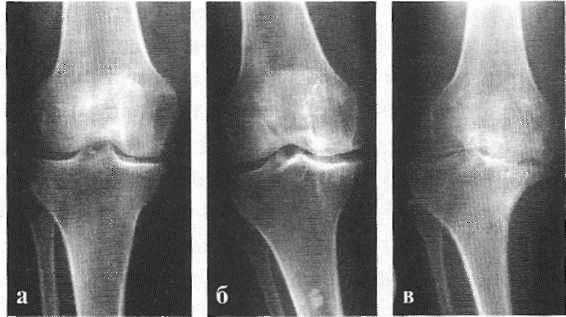

Рентгенологически отмечается характерная картина для этого заболевания. У молодых людей, когда еще не закрылась зона роста, видны неслившийся апофиз бугристости и отдельные костные фрагменты. Часто можно видеть значительную деформацию бугристости в виде «хобота». У более старших танцовщиков эта бугристость может иметь вид отдельных костных фрагментов.

Диагностика деформирующегося артроза коленного сустава несложна. Многие авторы выделяют триаду основных рентгенологических признаков, которым сопутствует соответствующая клиническая картина: неравномерное сужение суставной щели, склероз (уплотнение) субхондральных пластинок, краевые костные разрастания в области эпифизов костей и заострение межмыщелковых возвышений.

Выделяют три степени развития деформирующего артроза.

I степень — это склероз субхондральных пластинок, заострение межмыщелковых возвышений, умеренные боли в суставе после физической нагрузки, нежный хруст при движениях в суставе.

II степень - клинически определяется деформация коленного сустава, периодически возникает синовит, боль по суставной щели, пальпируются костные образования по суставным поверхностям, хромота возникает после физической нагрузки или при длительной ходьбе. Рентгенологически определяется сужение суставной щели, склероз субхондральных пластинок, заострение межмыщелковых возвышений и значительные костные разрастания. У артистов балета костные разрастания раньше возникают на надколеннике.

III степень — самая тяжелая степень развития деформирующего артроза. Клинически отмечается ограничение подвижности в коленном суставе, боли как после физической нагрузки, так и в покое, деформация сустава, выраженный хруст. В этой стадии синовиты бывают уже реже и сустав почти «сухой». Отмечается атрофия мышц бедра. На рентгенограмме суставная щель узкая, массивные костные разрастания, дегенеративные кисты в субхондральной зоне, суставные поверхности резко деформированы, явления подвывиха в суставе.